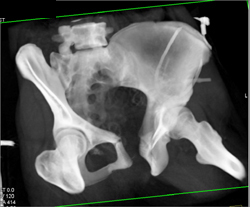

Sacral Fractures